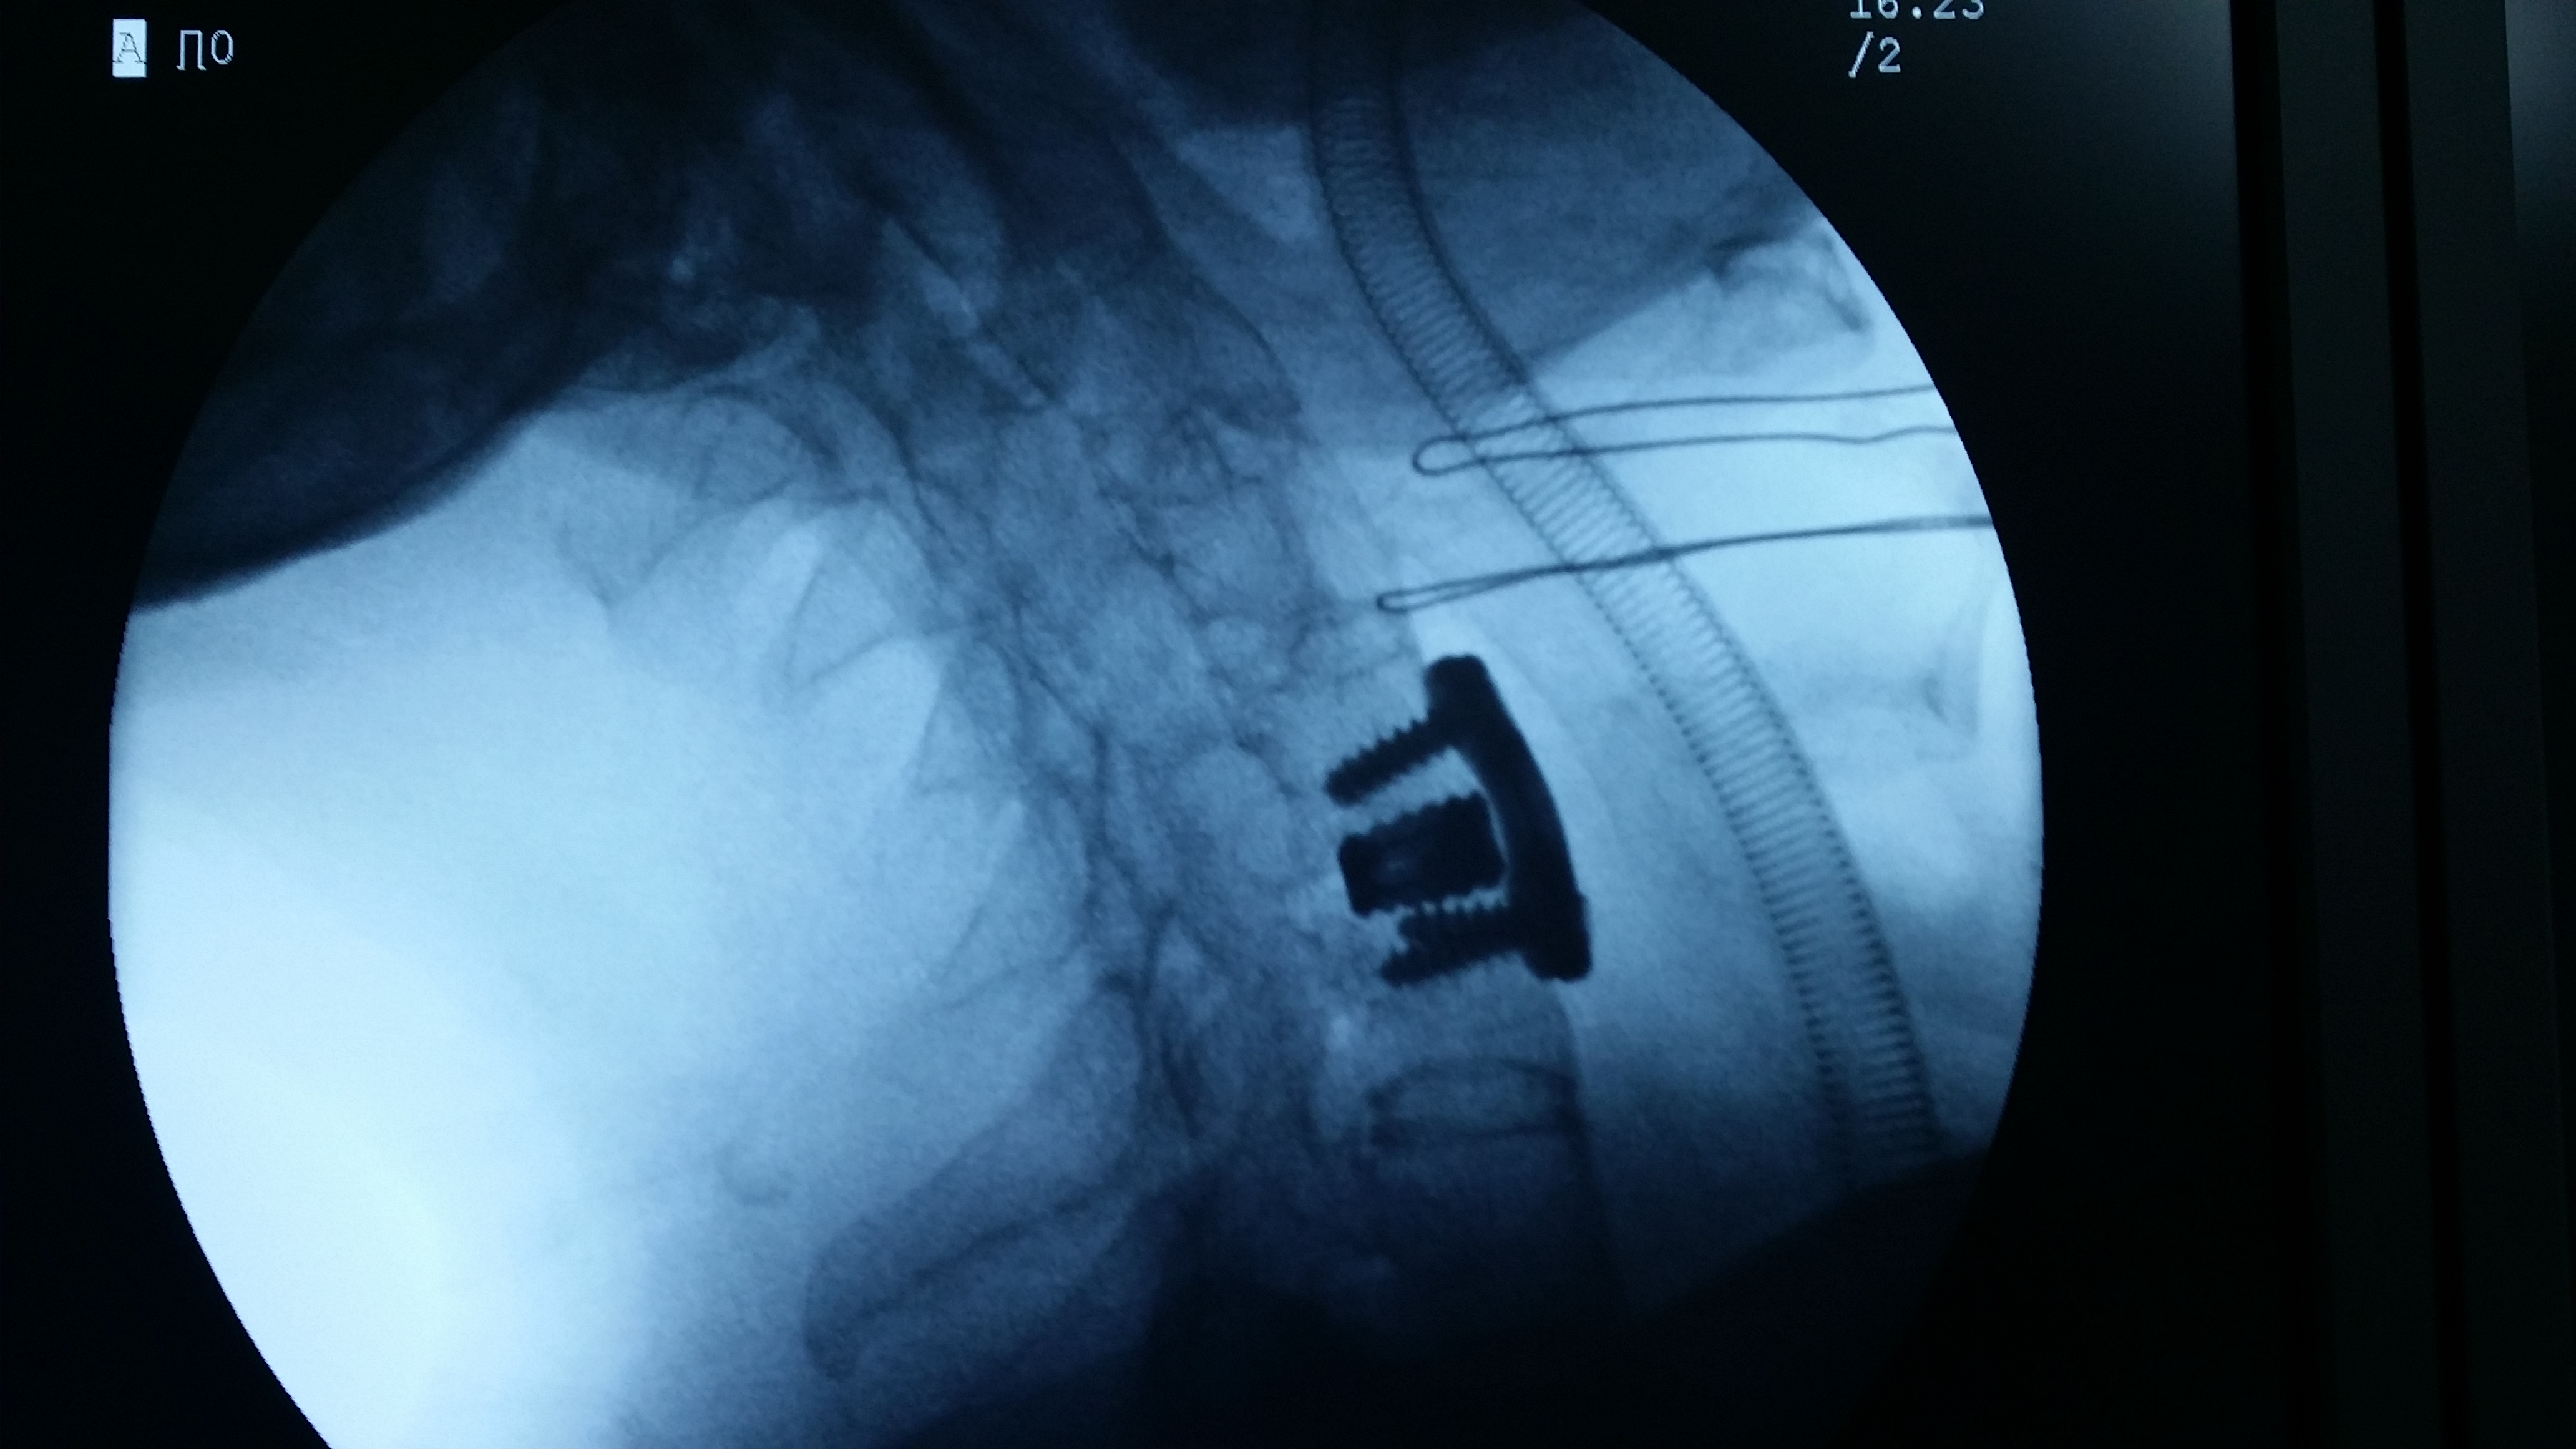

病人王某,男性,51岁,因“颈背部外伤后疼痛、双手麻木3小时”入院。系摩托车撞伤,先后咨询我市多家医院,均不敢收治。入院时病人双手中指、食指麻木,双上肢肌力Ⅲ级,双下肢肌力Ⅳ级。CT检查显示:颈5、6椎体及附件爆裂骨折、脱位并椎管狭窄,强直性脊柱炎。颈椎磁共振检查显示:颈髓受压,髓内未见明显高信号。我院即刻给予颈托外固定,完善术前检查,给予颈椎前路植骨融合内固定术,术后恢复好,术后影像复查显示骨折解剖复位,病人无不适感觉,行走同受伤前,20天后痊愈出院。

强直性脊柱炎的病理变化包括脊柱骨性强直、椎体骨质疏松等,导致脊柱骨脆性增加,较常人更容易发生骨折,该类骨折的损伤机制多属过伸伤,颈胸腰段均可发生,可导致四肢瘫、截瘫,致残率极高,死亡率高,对病人、家庭是巨大的灾难。高颈椎椎体骨折治疗风险高,技术难度大,一般医疗单位不愿意承担如此高风险的挑战。对该病人计划采用前后路联合固定治疗,因强直性脊柱炎所致的胸椎后突畸形显著,手术体位摆放困难,仅进行了前路植骨融合手术,术后强化颈托固定,以利骨性愈合。目前病人手术后三个月,复查CT显示:骨折解剖复位,有骨痂生长,无不良感觉,行走自如,与受伤前相比没有不适,劳动能力完全恢复,实现了回归社会的最好要求。

图三:术中颈椎侧位片